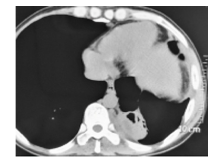

脓肿穿刺液革兰染色病原菌荚膜稍明显、未着色(透明光晕), 内有芽生孢子, 墨汁染色病原菌外层的光晕为厚厚的荚膜, 荚膜包裹着菌细胞, 提示可能是隐球菌(图1~图2)。患者血清隐球菌荚膜多糖抗原滴度为1∶ 1 024。背部及右臀部脓肿穿刺液直接接种血平板, 5 d后培养物由最初的白色逐渐转淡黄或棕黄、湿润粘稠, 状似胶汁(图3)。血液在BacT/ALERT需氧培养瓶中培养5 d后转种血平板, 5 d后生长的菌落形态与脓肿穿刺液一致。脑脊液墨汁染色、隐球菌荚膜多糖抗原及脑脊液培养均阴性。ID32 C和Vitek 2 Compact生化鉴定上述纯培养菌落, 结果为新型隐球菌(Cryptococcus neoformans), 鉴定率=99.9%, 符合率为T=0.84。

| 图1 脓汁革兰染色(× 1 000) 箭头所指为新型隐球菌。Fig.1 Gram staining of pus (× 1 000) Cryptococcus neoformans is showed by arrow. |

| 图2 脓汁墨汁染色(× 1 000) 箭头所指为新型隐球菌。Fig.2 Ink staining of pus (× 1 000) Cryptococcus neoformans is showed by arrows. |